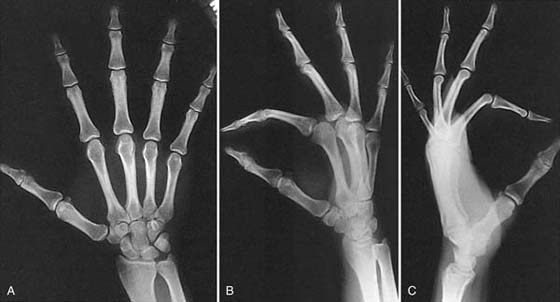

Routine studies of the hand consist of posteroanterior (PA), lateral, and oblique views, which are evaluated for bone density, bony lesions, fractures and dislocations, integrity of the articular surfaces and joint spaces, and irregularities of the soft tissue (Fig. 13-1).1

images

Figure 13-1 Routine views of the hand. A, Posteroanterior. B, Oblique. C, Lateral.